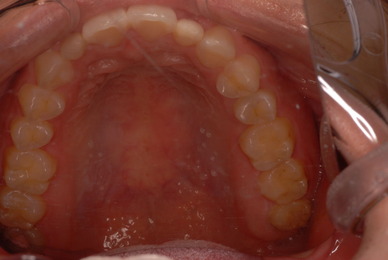

審美と言いましても、虫歯というばい菌を取り残せば駄目ですし、いくら綺麗にすると言いましても歯を沢山削ることはいけない事だと考えています。

ところが、これは接着の技法の向上からでしょうか。殆ど削らずにすみます。そしてその日にできる可能性が大なのです。